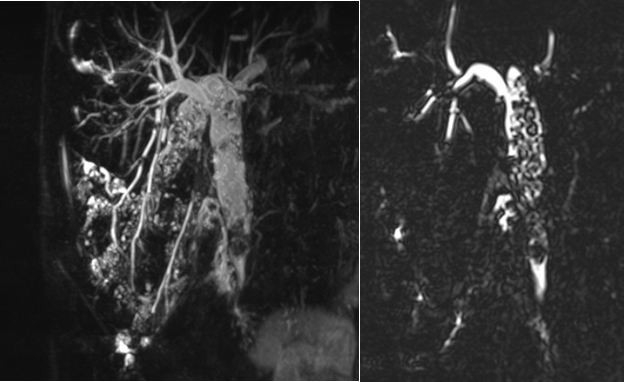

Daha önce safra kesesinden ameliyat olan Muttalip Örs (40), bir süredir karın sağ üst tarafında ağrı, ateş, sarılık, bulantı, iştahsızlık, beslenememe ve kilo kaybı şikâyetleri ile Selçuk Üniversitesi Tıp Fakültesi Hastanesine başvurdu. Hastanın yapılan tetkik ve değerlendirmelerinde karaciğer ve özellikle safra yolu testlerinde aşırı yükseklik olduğu, hem karaciğer içinde hem de karaciğer dışındaki safra yollarındaki çok sayıda taşın safra yollarını tıkadığı, hayatı tehdit edebilen safra yolu enfeksiyonu-kolanjit olduğu tespit edildi. Bu taşların temizlenmesi amacıyla, hasta anestezi eşliğinde uyutularak Selçuk Üniversitesi Tıp Fakültesi Gastroenteroloji ve Hepatoloji Bilim Dalı Öğretim Üyesi Doç. Dr. Gökhan Güngör tarafından ERCP işlemine alındı.

Konuyla ilgili açıklamada bulunan Doç. Dr. Gökhan Güngör, "Yaklaşık 45 dakika süren işlemde ağızdan kameralı duodenoskop cihazı ile girildi, safra yollarının ince bağırsaklara açılma yeri bulundu. Bu ağız sfinkterotomi adı verilen bir işlemle kesilerek genişletildi ve daha sonra safra yollarının içi balon ile sıvazlanarak büyüklükleri 3 mm ile 1,5 cm arasında değişen 100'den fazla safra taşı ince bağırsaklara düşürüldü" diye konuştu.